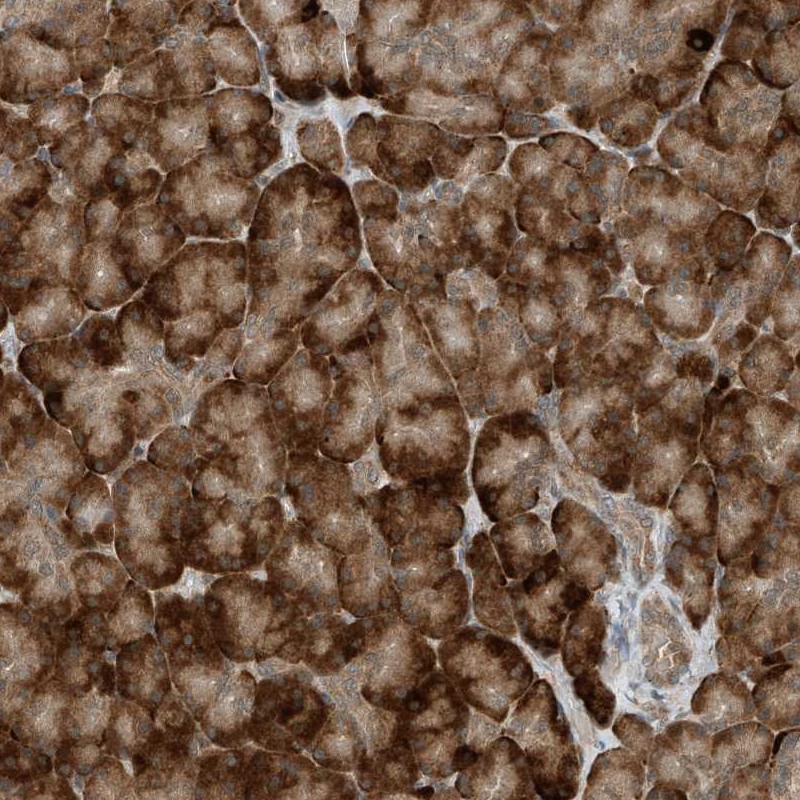

Immunohistochemical staining of human pancreas shows strong cytoplasmic positivity in exocrine glandular cells.